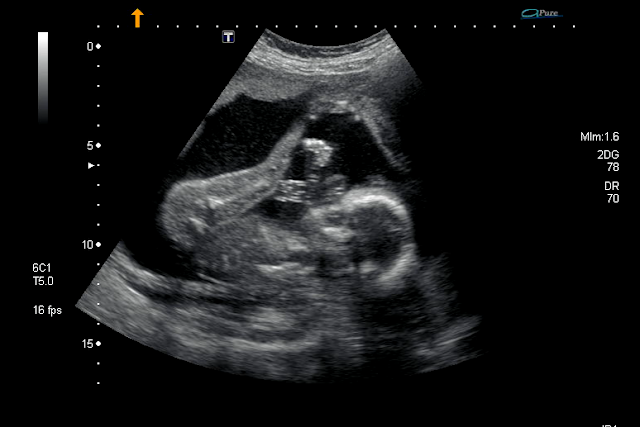

We were able to get some 3D images of Cooper yesterday and he looks identical to what Mason did. He may be a little bigger. Which I don't know if that is from being the second baby or from the gestational diabetes... We will find out soon on that... Cooper is breech just like Mason was and he has his feet up my his head. JUST LIKE MASON. I have a feeling they will look so much like twins. Let's just hope I can make it to at least 37 or 38 weeks. That is my goal.

The next photo is Cooper on top. Mason on bottom.

Had the anatomy scan back in July and it went perfect. This little nugget is measuring in the 60th percentile which is right along side of Mason. I have a feeling he will be about the same size. I'm a little disappointed in the anatomy scan this time because it literally lasted 15 min tops. When we were in GA with Mason they took tons of photos and even gave us some 3D photos as well. We didn't get any of that this time. BUT I am going in two weeks to get 3D photos done so I will have them with this one too!

Those are a few photos that we got.. We barely got any. I wish the ultrasound techs would show some compassion when doing these instead of cranking them out like machines. The ultrasound tech in GA was amazing so I think it skewed my opinion a little.

Here are a few photos from the ultrasound....